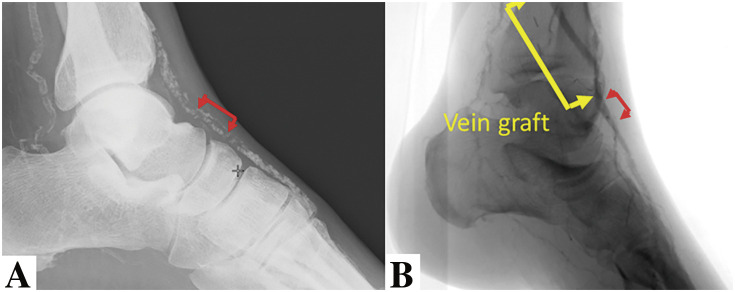

Infrapopliteal revascularization is generally performed for patients with chronic limb-threatening ischemia. As with revascularization in other fields, the indications for endovascular treatment (EVT) have expanded in recent years due to advances in endovascular devices and techniques. However, the optimal revascularization method must be selected based on (1) patient risk, (2) limb severity, and (3) anatomical pattern of disease. Therefore, vascular surgeons need to understand the characteristics of EVT and surgical treatment and improve their technical skills in both procedures. Here is an overview of the current methods of revascularization. (This is a translation of Jpn J Vasc Surg 2024; 33: 61-65).